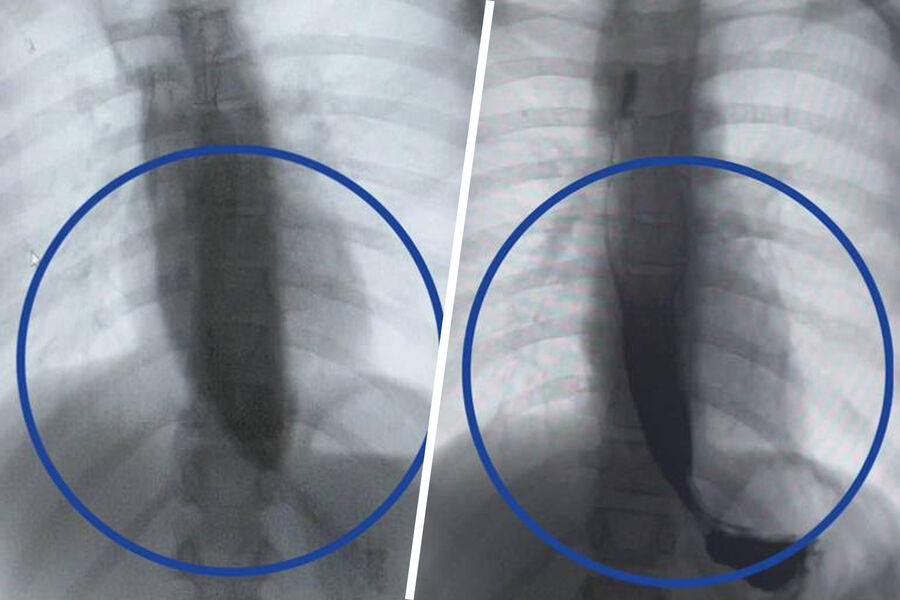

Врачи Детского клинического центра им. Л.М. Рошаля спасли девятилетнюю девочку с редким заболеванием — ахалазией кардии, из-за которого ее пищевод был расширен в пять раз. Об этом сообщили в пресс-службе минздрава Московской области.

Медики рассказали, что пищевод пациентки из-за патологии был расширен до четырех сантиметров, при норме в семь — десять миллиметров.

Операция прошла успешно, что уже на следующий день показало контрастное исследование — пища стала беспрепятственно поступать в желудок.